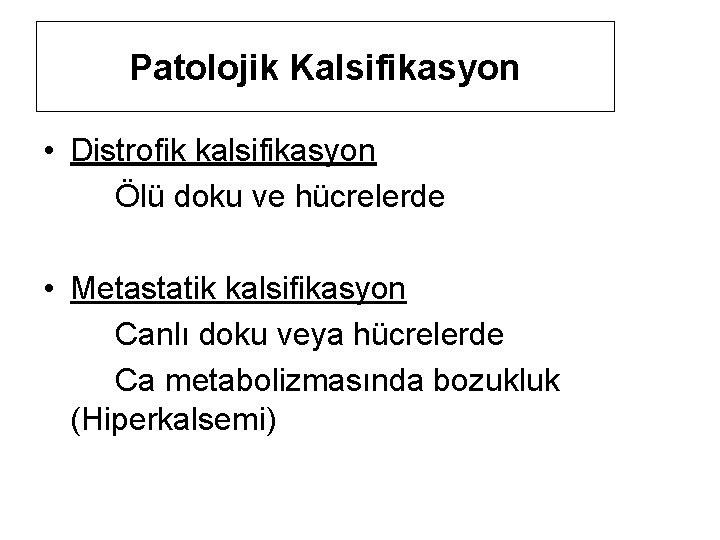

Patolojik Kalsifikasyon • Distrofik kalsifikasyon Ölü doku ve hücrelerde • Metastatik kalsifikasyon Canlı doku veya hücrelerde Ca metabolizmasında bozukluk (Hiperkalsemi)